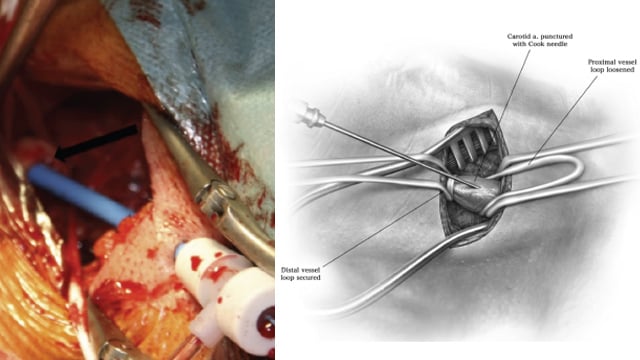

TAVI: alternative access

17 Nov 2025 – From PCR London Valves 2025

This session addresses alternative access routes for TAVI in patients with challenging vascular anatomies. It includes innovative approaches such as transapical TAV-in-TAV procedures, transcaval implantation in emergency settings, and techniques for patients with hostile iliofemoral access, showcasing adaptive strategies when conventional access is not feasible.